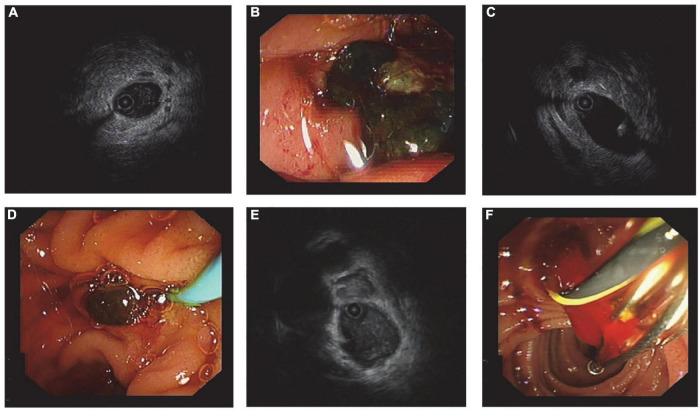

Before stones removal, there were a few patients in the three groups whose stones were not accurately evaluated. Both the size and the amount of the stones predicted in advance deviated from the final diagnosis. The accuracy of stone size prediction in the IDUS-BL, IDUS-ALC, and IDUS-AL groups was 86.9% (53/61), 85.5% (53/62), and 88.5% (54/61), respectively, while the accuracy of judging the number of stones in the three groups was 95.1% (58/61), 87.1% (54/62), and 83.6% (51/61), respectively. There was no significant difference among the three groups in the overestimation or underestimation of the size or amount of stones (all P > 0.05). Repeated lithotomies were done in 5, 9, and 9 cases of IDUS-BL, IDUS-ALC, and IDUS-AL group, respectively. No statistical difference was found in the frequency of RL and finding of RL (> or <3 mm calculus) among the three groups (Table 3 and Figures 2, 3)

Generally speaking, no residual stones were found during follow-up in the three groups, and no serious complications occurred. Compared with other researches, we achieved a lower complication rate, which can be partly attributed to the assistance of general anesthesia and proper indication for ERCP. The shorter average FT can be due to the personal experience of the operator. Moreover, RL during ERCP was not emphasized by other researchers. Our study showed that RL was related to the accuracy of stone prejudgment. Inaccurate prejudgment led to a higher RL rate. Also, both lithotripsy and bile duct diameter were relevant to RL. After lithotripsy, many stone fragments were produced, so it is difficult to judge whether all the stones were removed. Previous studies have suggested that biliary stenting after lithotripsy is safe, which is consistent with our experience (ref. 20). When the bile duct is too wide, it can lead to inadequate angiography, making the basket empty out and the balloon not fit the bile duct wall. The high sensitivity of IDUS makes it possible to detect stones 1–2 mm in size. We are also concerned about whether the stones removed in RL are larger than 3 mm, because stones larger than 3 mm might cannot be automatically discharged. The high sensitivity of IDUS may also lead to misjudgment. Thick bile, guidewire, blood clot, and bubbles need to be differentiated from stones (Figure 3).